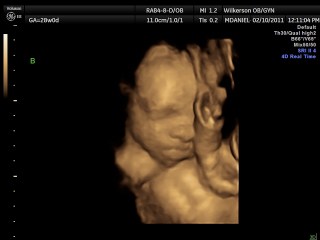

We had our 4-D ultrasound today. James would not cooperate at all but Jackson did. He was so precious he kept his hand over his face though. It was so neat. They are definitely cramped in there. We go back Monday and hopefully James will work with us. Here our a few pictures we have more but they are video rather than pictures.

Here is sweet Jackson: